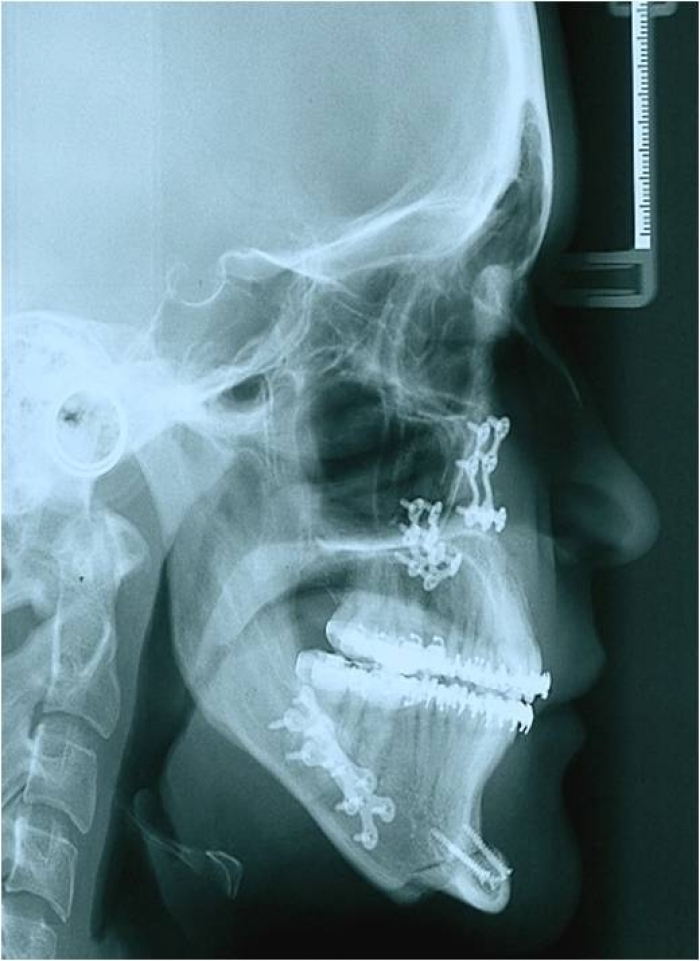

Telerradiografia após a cirurgia